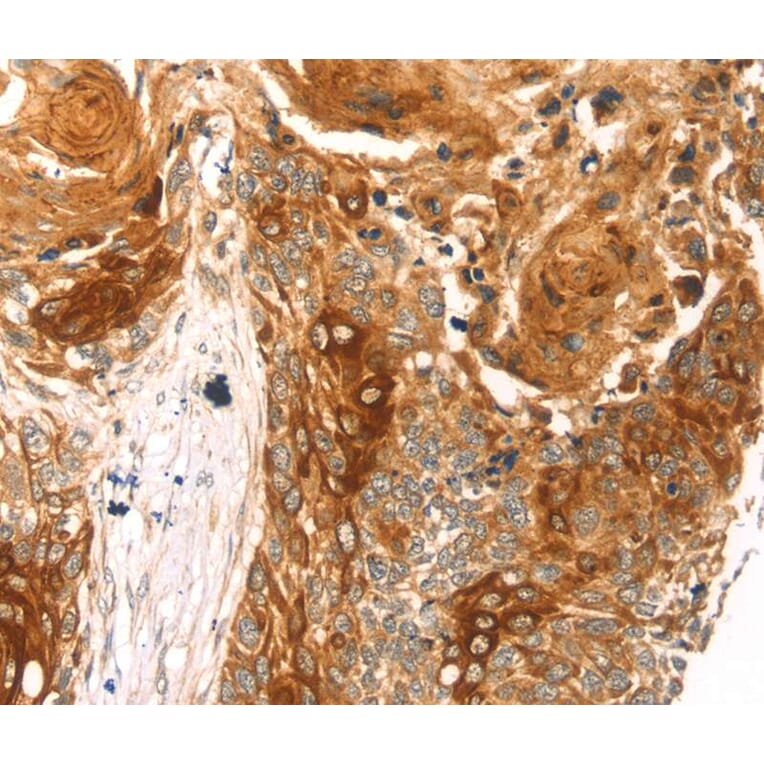

Immunohistochemistry - Anti-THAP9 Antibody (A46348)

Immunohistochemical analysis of paraffin-embedded Human oesophagus cancer tissue using #40243 at dilution 1/20.